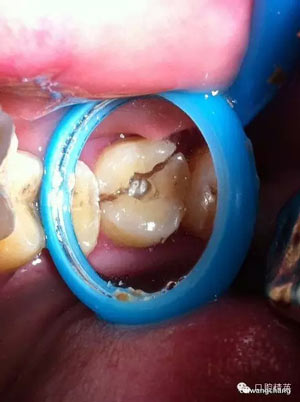

復(fù)位后可見基本對(duì)齊

玻璃離子墊底

超硬樹脂材料呈啞鈴狀充填,觀察1-2周無(wú)反應(yīng)給予牙體預(yù)備烤瓷冠修復(fù)